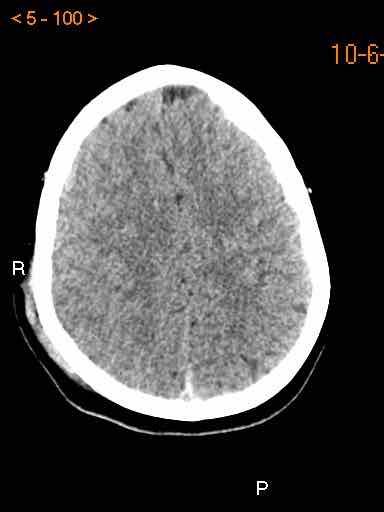

Tụ máu dưới màng cứng đồng tỷ trọng

Khi tụ máu dưới màng cứng tiến triển theo thời gian, tỷ trọng của khối tụ máu sẽ giảm dần và có thể tương đương với tỷ trọng của nhu mô não, khiến việc phát hiện tổn thương trở nên khó khăn.

Đây là trường hợp tụ máu dưới màng cứng đồng tỷ trọng rất khó phát hiện (các mũi tên).

Lưu ý rằng ở mức cắt cao hơn có tụ máu dưới màng cứng hai bên.